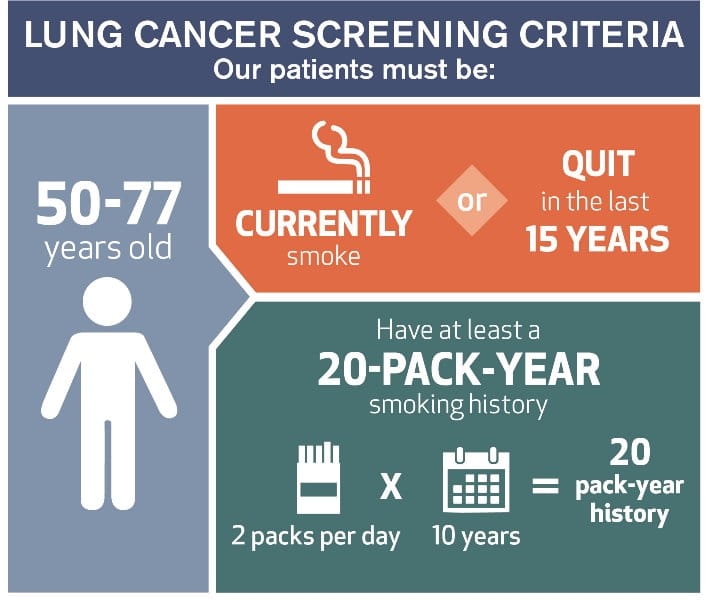

Lung Cancer Screening X Ray

Experience the clarity of Lung Cancer Screening X Ray with our curated collection of comprehensive galleries of images. featuring understated examples of photography, images, and pictures. designed to emphasize clarity and focus. Discover high-resolution Lung Cancer Screening X Ray images optimized for various applications. Suitable for various applications including web design, social media, personal projects, and digital content creation All Lung Cancer Screening X Ray images are available in high resolution with professional-grade quality, optimized for both digital and print applications, and include comprehensive metadata for easy organization and usage. Our Lung Cancer Screening X Ray gallery offers diverse visual resources to bring your ideas to life. Comprehensive tagging systems facilitate quick discovery of relevant Lung Cancer Screening X Ray content. Multiple resolution options ensure optimal performance across different platforms and applications. Time-saving browsing features help users locate ideal Lung Cancer Screening X Ray images quickly. The Lung Cancer Screening X Ray archive serves professionals, educators, and creatives across diverse industries. Instant download capabilities enable immediate access to chosen Lung Cancer Screening X Ray images. Whether for commercial projects or personal use, our Lung Cancer Screening X Ray collection delivers consistent excellence. Professional licensing options accommodate both commercial and educational usage requirements.